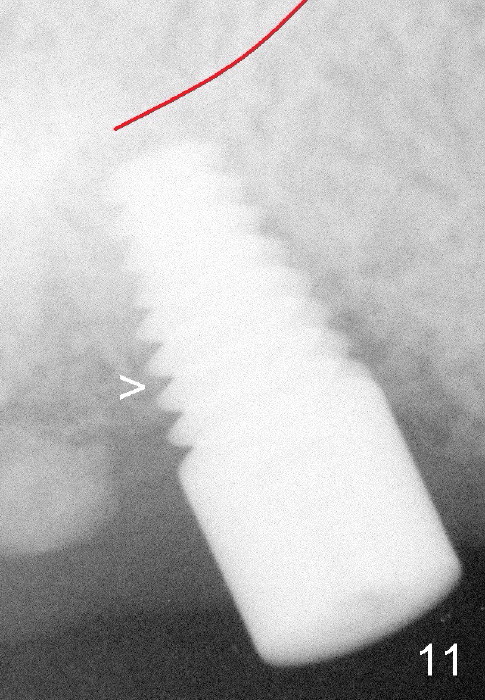

Fig.11: The implant appears to have osteointegrated 3 months postop (>).